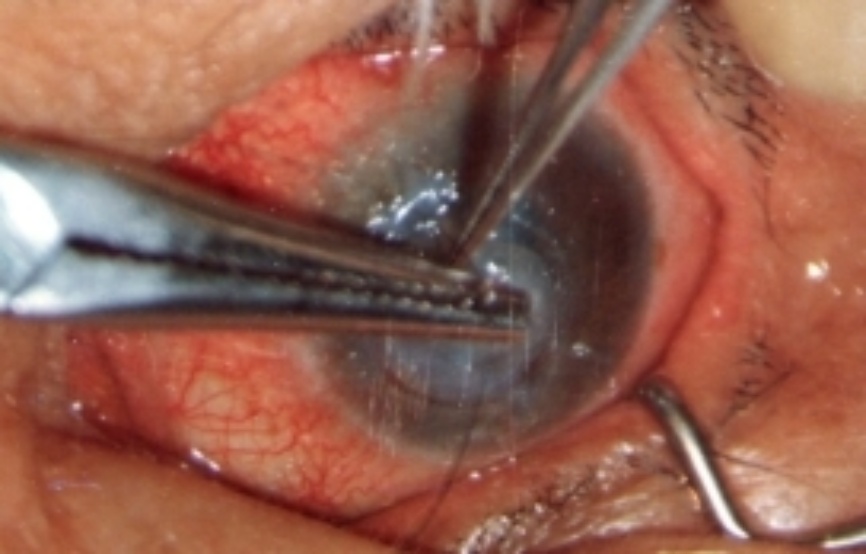

3.2. 手术方法和术后处理

在手术显微镜下(或用手术扩大镜),彻底切除病变组织,做好植床,用划界的环钻钻取全层鹅角膜后刮掉内皮层,或用角膜剪剪取整个鹅角膜刮掉内皮层。再按切除病变后植床的形状和大小做成鹅角膜移植片,用9个0单丝尼龙线间断加连续缝合固定移植片。结膜下注入庆大霉素和氟美松,压迫绷带包扎一周。每天更换敷料,涂1%阿托品眼膏和四环素可的松眼膏。口服地塞米松,一周拆除间断缝线,1~2个月拆除连续缝线。

附 录

鹅角膜板层移植部分病例

第三例